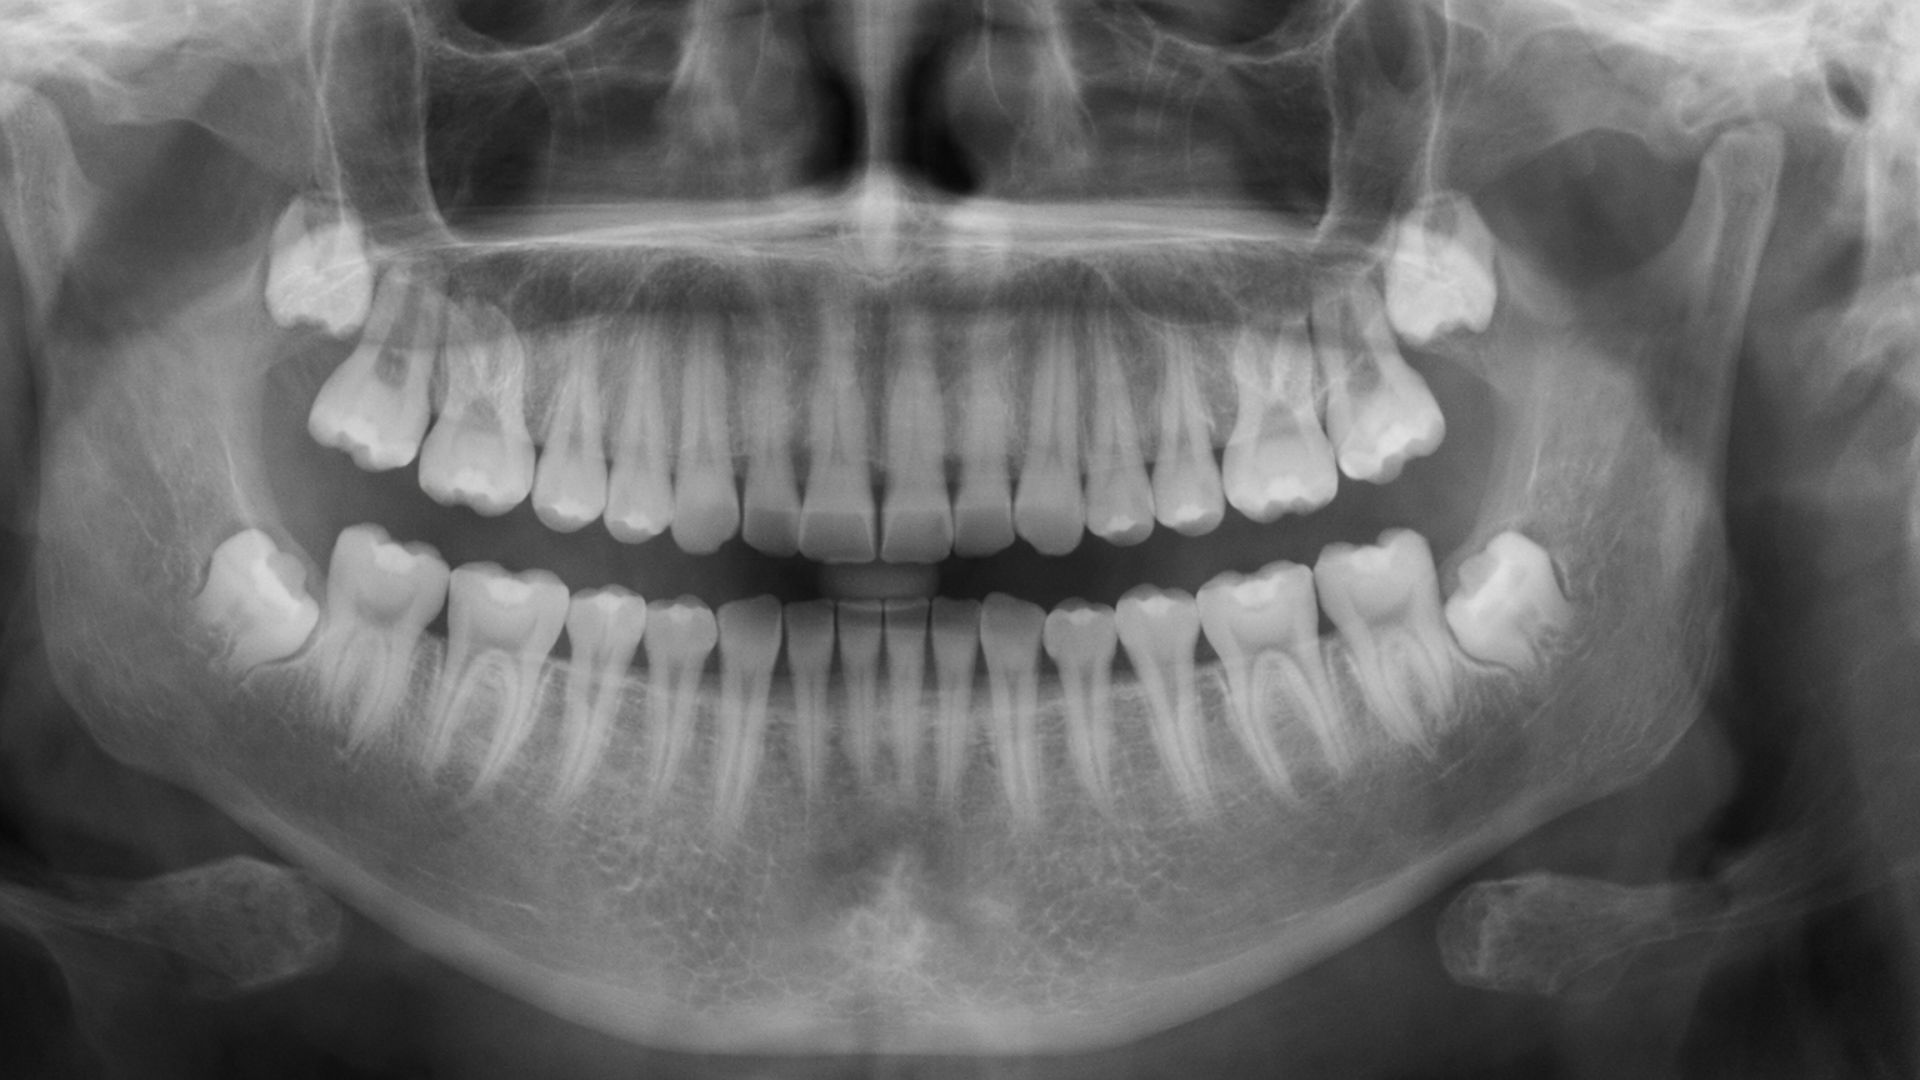

Răng khôn là răng nào hay răng khôn là răng số mấy? Răng khôn hay còn gọi là răng hàm thứ ba, chính là răng số 8 trên cung hàm. Trong hệ thống đánh số răng tiêu chuẩn, mỗi bên hàm trên và hàm dưới đều có một chiếc răng khôn, nằm ở vị trí cuối cùng của cung hàm. Vậy răng khôn mọc khi nào?

Thời điểm răng khôn bắt đầu mọc thường rơi vào độ tuổi từ 17 đến 25 tuổi - khi con người đã bước vào giai đoạn trưởng thành. Sở dĩ, những chiếc răng này được gọi là răng khôn vì mọc khi người ta đã khôn lớn, có nhận thức rõ ràng hơn về sức khỏe và cuộc sống. Tuy nhiên, không phải ai cũng mọc răng khôn đúng độ tuổi này. Một số trường hợp có thể mọc sớm hơn hoặc muộn hơn, thậm chí không mọc hẳn.

Theo các tài liệu nha khoa, khoảng 90% người trưởng thành sẽ có ít nhất một chiếc răng khôn mọc lên nhưng thời gian và cách mọc ở mỗi người là khác nhau, phụ thuộc vào yếu tố di truyền, kích thước hàm và tình trạng sức khỏe tổng thể.

Thông thường, một người trưởng thành có tối đa 4 chiếc răng khôn bao gồm 2 chiếc ở hàm trên và 2 chiếc ở hàm dưới, mỗi bên một chiếc. Tuy nhiên, không phải ai cũng mọc đủ 4 chiếc. Có những trường hợp chỉ mọc 1 - 2 chiếc hoặc thậm chí không mọc chiếc nào do thiếu mầm răng bẩm sinh. Ngược lại, một số ít người có thể mọc thêm răng khôn thừa nhưng điều này khá hiếm gặp.